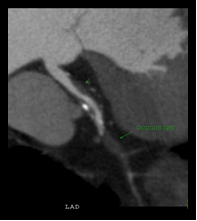

This latest 64 slice CT machine has a special role in Cardiac Angiography, since this investigation has been found to be a viable alternative to catheter angiography. Cardiac coronary Angiography has been found to be highly sensitive and specific in diagnosing coronary artery stenosis, stenosis in coronary stents and occluded coronary bypass grafts. The added advantage of Cardiac CT angiography is that it is completely non invasive, unlike catheter angiography. Also it is the modality to detect and characterize silent non-obstructive atherosclerotic plaques, which may be associated with adverse outcome and cannot be picked up on catheter angiography

Normal LAD